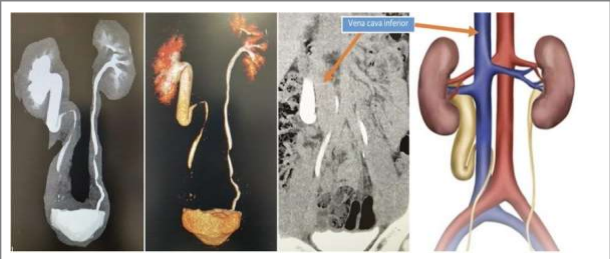

To eliminate the possibility of a ureteral stone, I ordered a CT scan of the abdomen without contrast. Although this confirmed the absence of a stone, it revealed an unusual path of the right ureter. As a result, a follow-up CT scan with contrast was required. It showed right- sided- hydronephrosis and hydroureter because the right ureter showing Kinking and passing behind the inferior vena cava at the level of lower L3 vertebra. The Ureter exits medially between the vena cava and the aorta to return to its normal position. It led to the diagnosis of a rare condition: a retrocaval ureter.

The distal ureter was not clear in the CT scan, because of this I performed a cystoscopy with retrograde Ureterography.

The ureter passes behind the vena cava inferior leading to varying degrees of ureteral compression. There are clinical types: a common Type I with a low loop and kinking of the proximal ureter producing obstruction and a rare Type II with a high loop where there is no kinking and no obstruction (5).

Type I: The slightly commoner form has a moderate or severe hydronephrosis and an ‘S’ or ‘fishhook’ deformity of the ureter at the point of obstruction. They demonstrate that the point of obstruction is placed some distance from the lateral margin of the inferior vena cava.